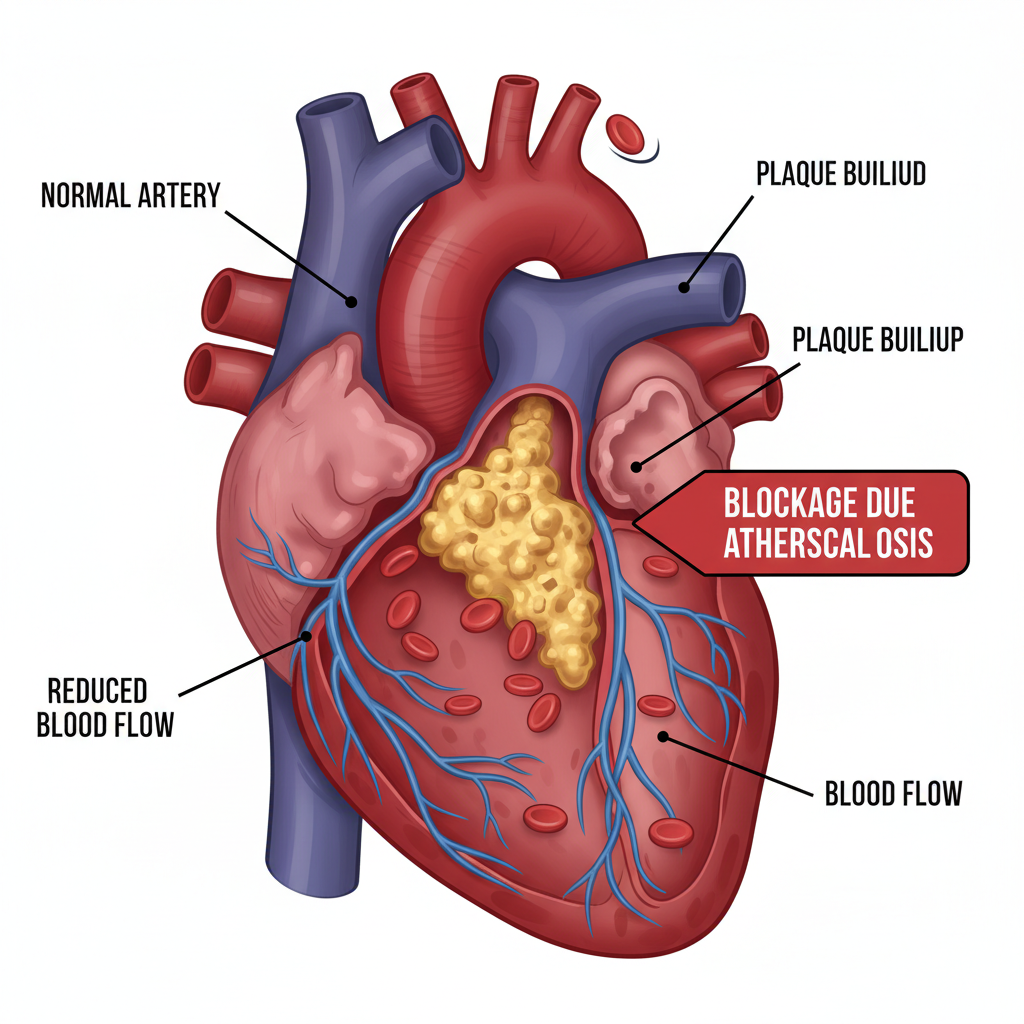

Nhận biết sớm 5 dấu hiệu bệnh mạch vành: đau thắt ngực, khó thở, đau tim, nhịp tim bất thường, đổ mồ hôi và chóng mặt. Khám tim mạch định kỳ tại Phòng khám BS Phạm Xuân Hậu để được chẩn đoán và điều...

Nhận biết sớm 5 dấu hiệu bệnh mạch vành: đau thắt ngực, khó thở, đau tim, nhịp tim bất thường, đổ mồ hôi và chóng mặt. Khám tim mạch định kỳ tại Phòng khám BS Phạm Xuân Hậu để được chẩn đoán và điều...

Bệnh động mạch vành không đau ngực, hay còn gọi là nhồi máu cơ tim thầm lặng, là một trong những căn bệnh nguy hiểm mà nhiều người không hề hay biết. Dưới đây là thông tin cần thiết giúp bạn hiểu rõ...

Bệnh động mạch vành không đau ngực, hay còn gọi là nhồi máu cơ tim thầm lặng, là một trong những căn bệnh nguy hiểm mà nhiều người không hề hay biết. Dưới đây là thông tin cần thiết giúp bạn hiểu rõ...

Bệnh động mạch vành đang gia tăng tại Việt Nam và là nguyên nhân hàng đầu gây tử vong. Cùng tìm hiểu cách nhận biết sớm và bảo vệ trái tim.

Bệnh động mạch vành đang gia tăng tại Việt Nam và là nguyên nhân hàng đầu gây tử vong. Cùng tìm hiểu cách nhận biết sớm và bảo vệ trái tim.

Nhồi máu cơ tim (NMCT) là bệnh lý nguy hiểm do tắc nghẽn mạch vành. Các dấu hiệu bao gồm đau thắt ngực (đau như bóp nghẹt sau xương ức, lan lên vai trái, kéo dài trên 20 phút), vã mồ hôi, khó thở,...

Nhồi máu cơ tim (NMCT) là bệnh lý nguy hiểm do tắc nghẽn mạch vành. Các dấu hiệu bao gồm đau thắt ngực (đau như bóp nghẹt sau xương ức, lan lên vai trái, kéo dài trên 20 phút), vã mồ hôi, khó thở,...